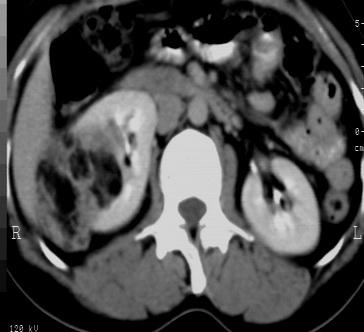

标题: CT24780:女 41岁 右肾多发低密度占位性病灶 [打印本页]

标题: CT24780:女 41岁 右肾多发低密度

女 41岁 超声检查:右肾多发实质性包块,性质待查(提示:错构瘤或其它病变),临床病史不详。